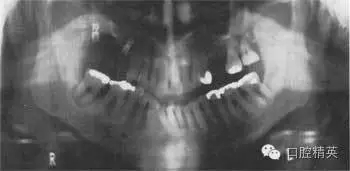

圖38.3 牙齒全口牙位曲面體層X線片顯示的治療結(jié)果

患者接受了一系列治療,療效如圖38.3。左下頜第一磨牙進(jìn)行了截根術(shù),右下頜第一磨牙進(jìn)行了半切術(shù)。這樣就消除了根分叉使患者能夠清潔。牙根周圍的炎癥得到解決。